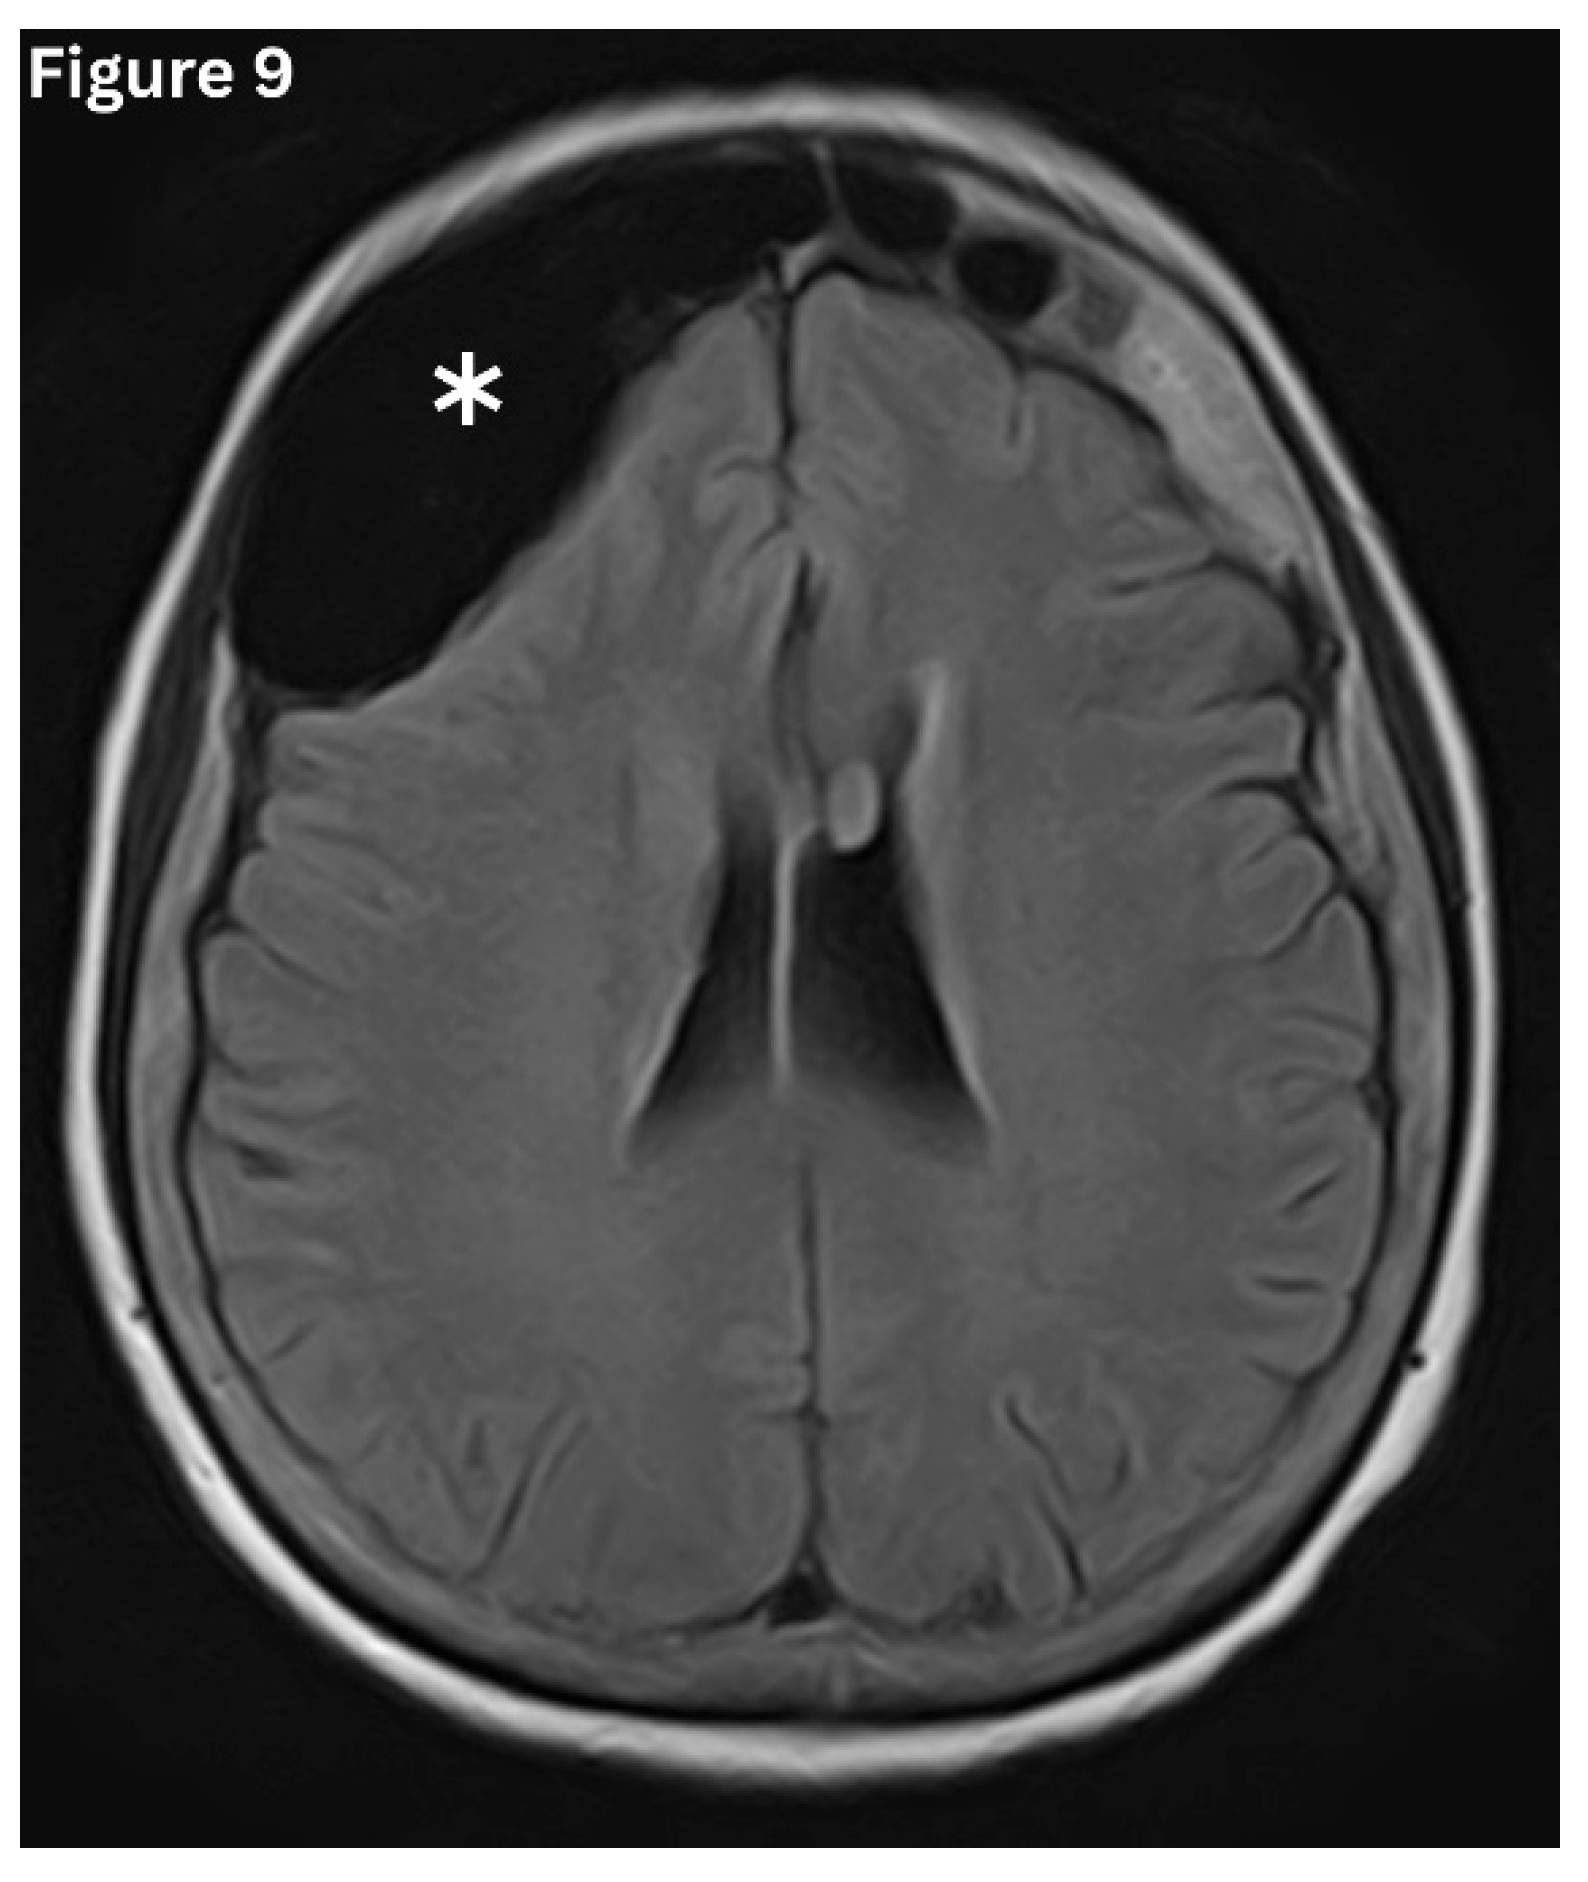

Figure 9. Axial MRI- FLAIR image shows abnormal pneumatisation of the right frontal sinus.

Pneumosinus dilatans (PSD)is characterised by abnormal expansion of a paranasal sinus beyond its normal boundaries, while maintaining normal mucosal lining and preserving bony walls. (Figure 9 and Figure 10) It is a developmental variant and is most often seen in the frontal, sphenoid, and maxillary sinuses. PSD most often affects a single sinus rather than multiple cavities, with isolated involvement reported in nearly 80% of cases [14]. It is frequently detected incidentally on imaging. However, some may present with frontal bossing and a spectrum of visual disturbances, including proptosis, diplopia and headache. This predisposes to recurrent episodes of sinusitis due to impairment of normal sinus drainage [14].